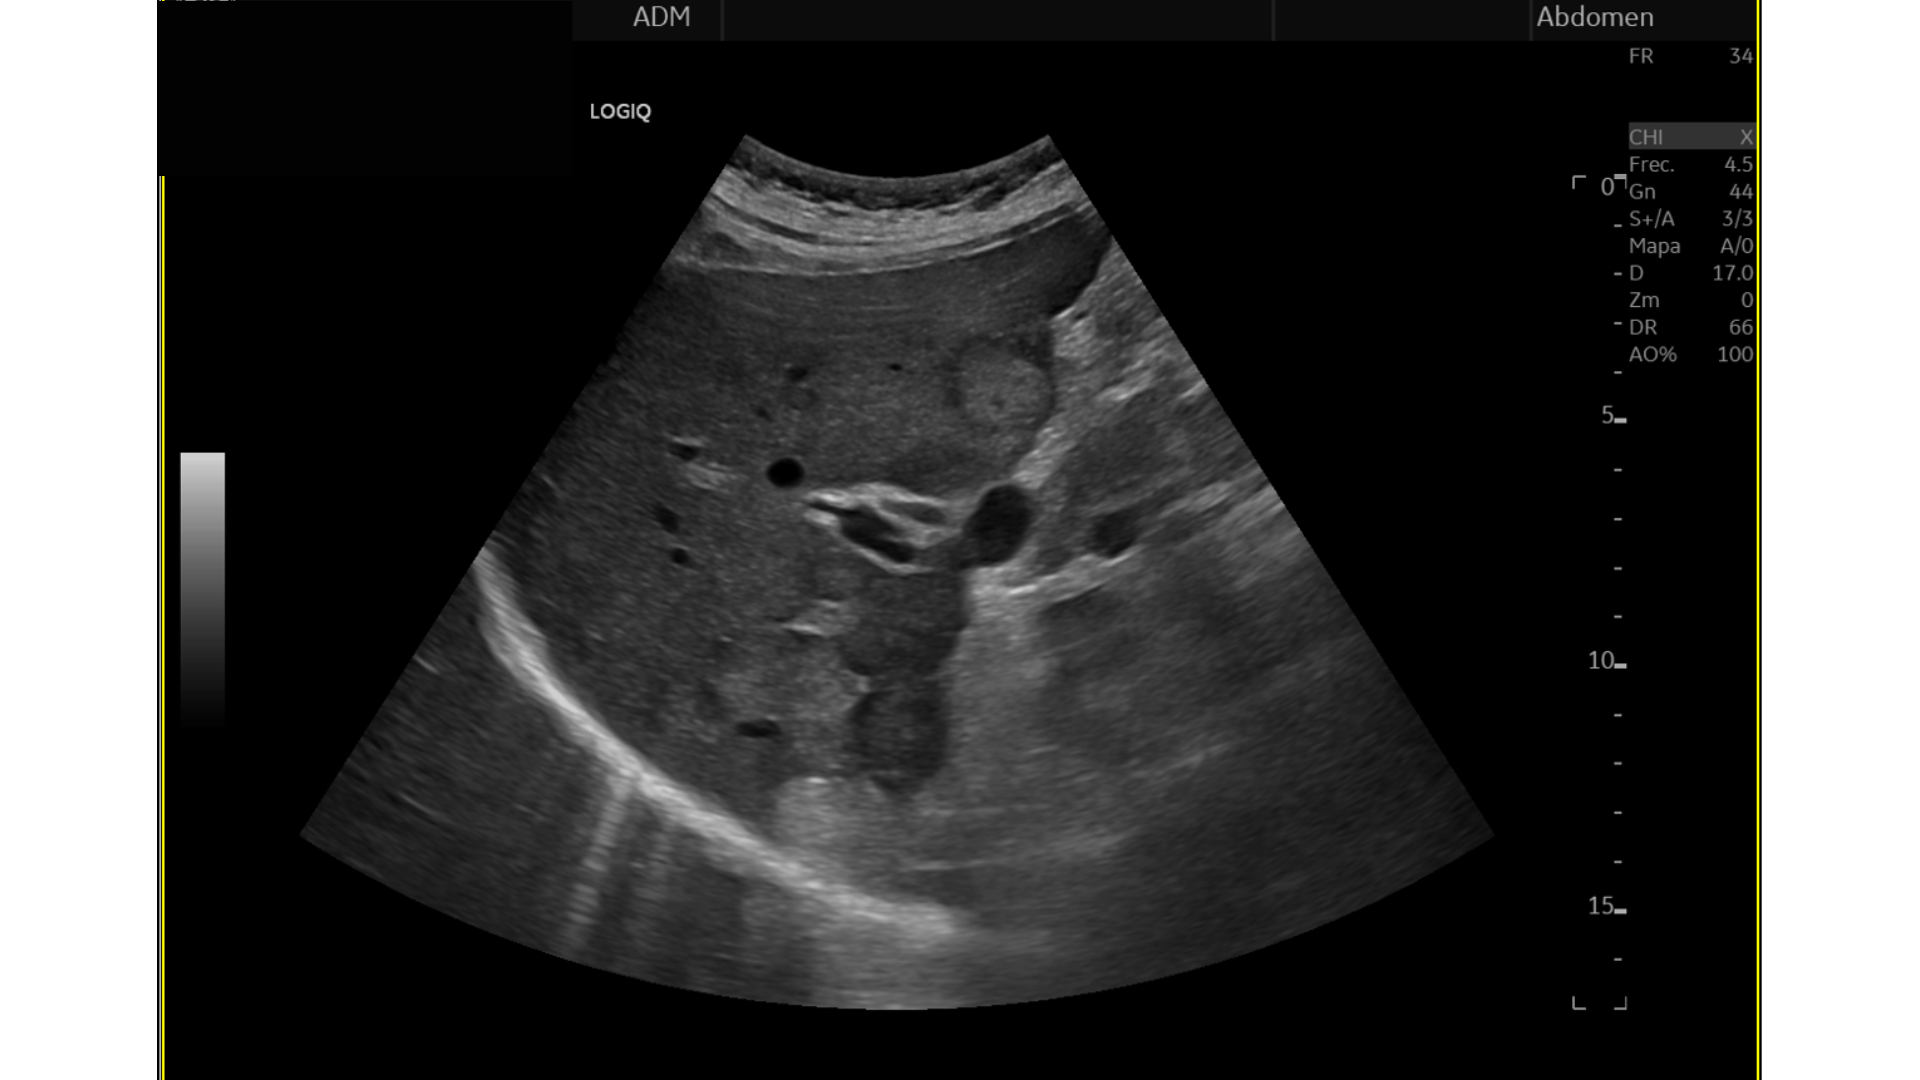

Eco Abdominal: Múltiples imágenes nodulares heterogéneas en ambos lóbulos hepáticos sugestivas de M1. Destaca imágen nodular, hipoecogénica en cabeza/cuerpo de páncreas de aprox. 17 mm, podría corresponderse con proceso neoformativo primario.